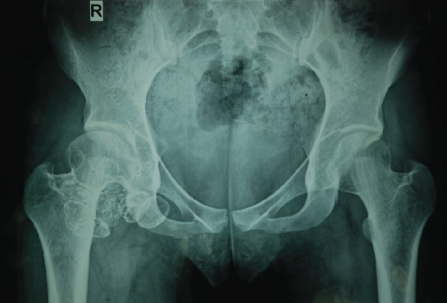

A 27-year-old previously healthy woman presented with a 2-year history of progressive right hip pain. The pain was described as deep, aching, and exacerbated by activity, with no history of antecedent trauma. Physical examination revealed a right coxalgic gait pattern with visible atrophy of the right thigh musculature. The range of motion assessment demonstrated preserved but painful movement in all planes, with particular limitation at terminal ranges. The patient reported functional impairment affecting daily activities and work performance. Plain radiographs of the right hip revealed multiple radiopaque loose bodies distributed throughout the hip joint space, with mild medial joint space narrowing and early osteophyte formation consistent with secondary degenerative changes (Fig. 1).

Figure 1: Multiple loose bodies in the right hip joint with narrowing of medial joint space.